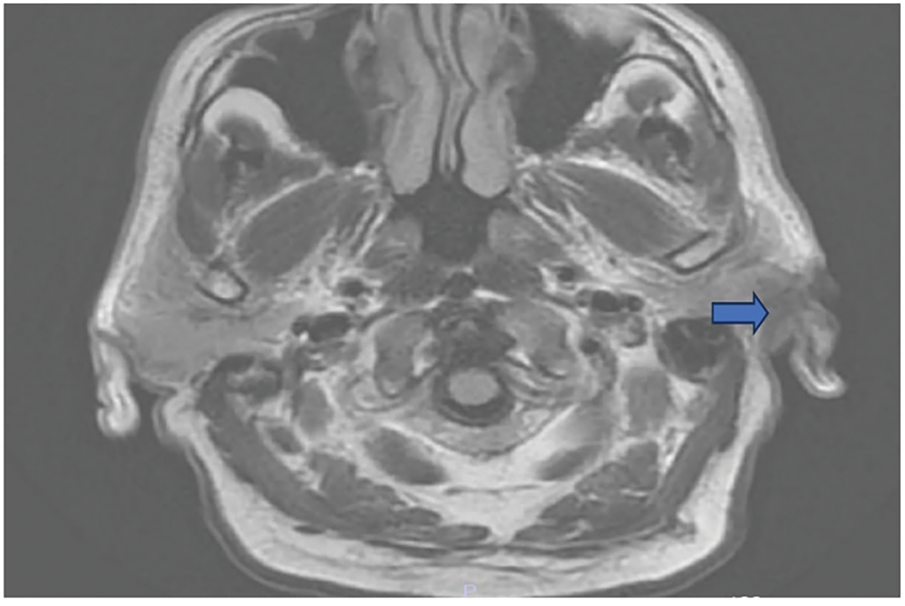

A 72-year-old male under androgen deprivation therapy for high-risk prostate cancer (Gleason 4+5, prostate specific antigen [PSA] 260 ng/mL) presented with body pain and lower urinary symptoms. Despite castration-level testosterone, PSA remained elevated. Prostate spesific membrane antigen (PSMA) revealed multiple skeletal metastases and a suspicious frontal lobe lesion. Cranial MRI confirmed a parieto-occipital bone lesion suggestive of metastasis (Figure 4).

FIGURE 4. Metastatic lesion in the T1 axial bone window reported as compatible with prostate cancer observed in the left parieto-occipital bone (shown with blue arrow)

Prostate cancer commonly metastasizes to bone, but involvement of the skull or cranial bones is uncommon. Brain or skull metastases from prostate cancer, while rare (<2% incidence in clinical series), do occur and have been reported even when serum PSA is not markedly elevated.15 For instance, isolated brain metastases have been documented in prostate cancer patients who had normal PSA levels at presentation.16 In our case, a castration-resistant prostate cancer patient developed a metastasis to the parieto-occipital bone, detected on PSMA and MRI. This scenario, although rare, has been observed in advanced prostate cancer—often manifesting as skull base metastases with cranial nerve palsies or as dural metastases mimicking meningiomas or subdural hematomas.17